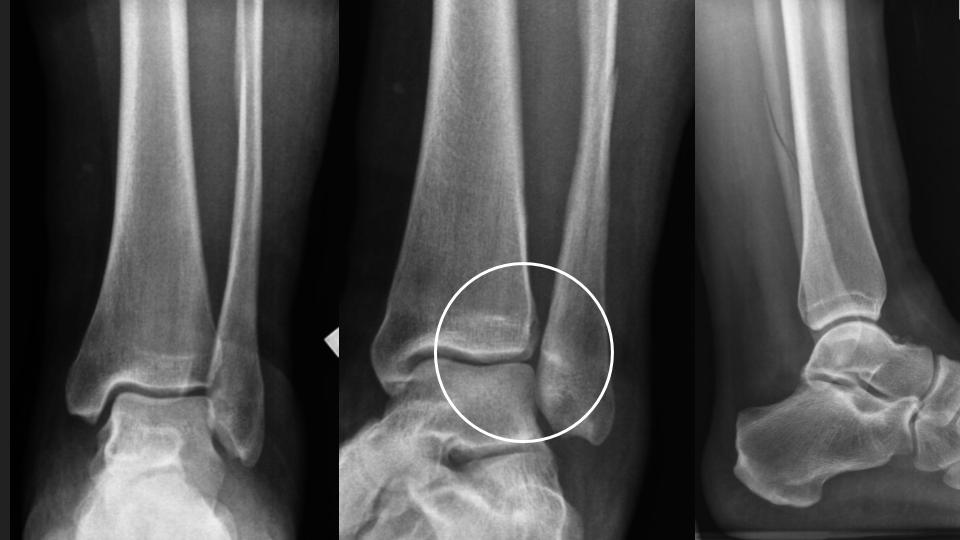

25F 10d after fall with fibular fracture

There is non displaced distal fibular shaft fx (see XR). There is a partial tear of the interosseous membrane (red arrows). There is complete AITFL rupture (white arrows). Gr I sprain of the PITFL and Laciniate ligaments. I think there is double band morphology of the ATFL, with a complete tear of one band and the other band intact (blue arrow). There is partial tear of the CFL (yellow arrow)...generally the CFL tears after the ATFL. The key point is that there should ALWAYS be overlap of the distal tibial and fibula in the Oblique or Mortise view...in this Obl view there is none. Syndesmotic Complex injury should have been suspected on the basis of the XR findings.